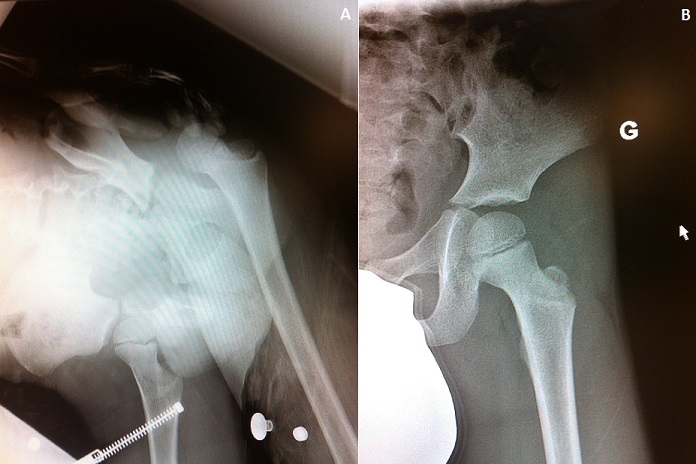

Il s'agit d'un enfant de 5ans, sans antécédent pathologique notable, victime d'une chute de sa hauteur à la cour de l’école, occasionnant chez lui une douleur et une impotence fonctionnelles totales du membre inférieur gauche. L'examen clinique trouve un membre inférieur raccourci en adduction et rotation interne. Le bilan radiologique montre une luxation postérieure pure de la hanche sans lésion associée (A). La prise en charge en urgence a consisté en une réduction de la luxation sous anesthésie générale (B), suivie de la mise en place d'une traction non collée pendant 3 semaines.